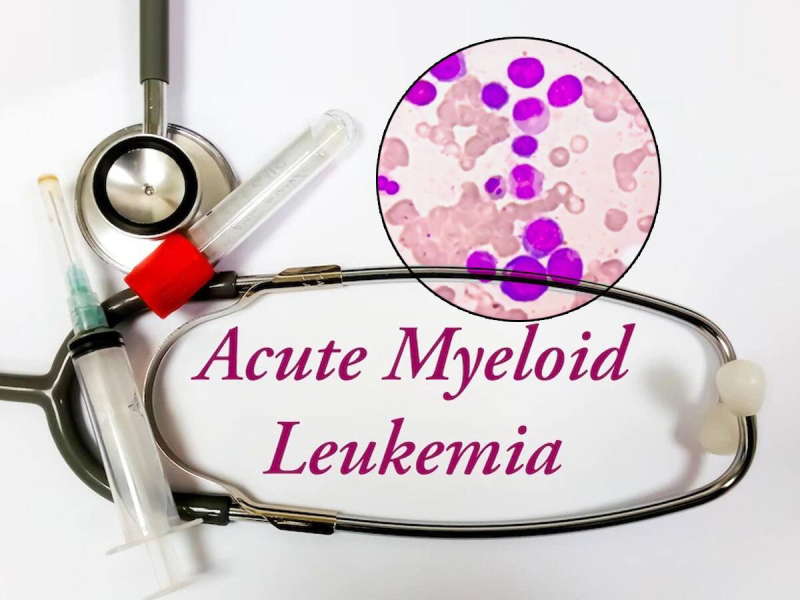

Tumors & Cancers

Discover symptoms & explore medicines and treatment options. Also read expert health articles about symptoms, the latest research, medicines and alternative treatments for every disease and medical condition.